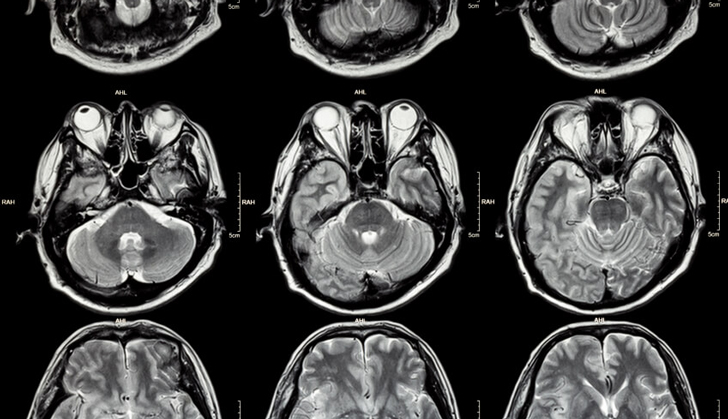

La muerte encefálica, también llamada muerte cerebral, se define como el cese completo e irreversible de la actividad encefálica o cerebral.

La muerte encefálica, también llamada muerte cerebral, se define como el cese completo e irreversible de la actividad encefálica o cerebral. Concepto, definición y diagnóstico clínico dr. Use custom templates to tell the right story for your business. En 1959 se postuló el coma depassé (coma irreversible) en 23 casos con pérdida de conciencia (coma). Potenciales evocados multimodales amati 4 ch. La muerte encefálica sobreviene por lesiones traumáticas encefálicas, hemorragia subaracnoidea, maltrato infantil o la asfixia. Muerte encefálica o muerte cerebral. Savesave muerte encefalica for later.

La muerte cerebral es lo que se conoce como el cese o finalización irreversible de todas las funciones encefálicas del paciente, sin embargo, algunas la muerte cerebral es ocasionada por lesiones craneoencefálicas traumáticas severas o por lesiones de tipo hemorrágicas que pueden generar. Que requisitos se debe cumplir para ser considerada muerte encefalica. La definición y determinación de la muerte han sido una historia de incertidumbre, siendo pocas veces una tarea fácil y nunca una empresa segura. Muerte encefalica • la muerte encefálica (me) se define como el cese irreversible de todas las funciones de los hemisferios cerebrales y del tronco. En 1959 se postuló el coma depassé (coma irreversible) en 23 casos con pérdida de conciencia (coma). 5 invalidan la muerte encefalica signos de descerebración (bulboprotuberancial) signos de decorticación (tronco cerebral) convulsiones. Savesave muerte encefalica for later. Muerte encefálica o muerte cerebral. La muerte encefálica, también llamada muerte cerebral, se define como el cese completo e irreversible de la actividad encefálica o cerebral. Record and instantly share video messages from your browser. En el momento actual la muerte se considera el momento a partir del cual cesan las funciones cerebrales de forma permanente e irreversible. Estado de cese prolongado e irreversible de toda la actividad encefálica, se incluyen las funciones bajas del tronco del encéfalo con ausencia completa de los movimientos voluntarios, respuesta a estímulos, reflejos del tronco del encéfalo, y respiraciones espontáneas. Se trata de un hombre de 41 años, pareja de una vecina de la familia de la menor, víctima de una bala perdida durante los festejos de navidad.